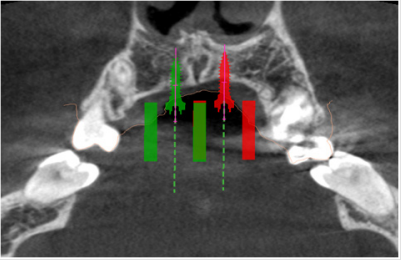

A female patient presented in our office for a consult. Her oral hygiene status needed improvement especially in the frontal upper area. Intraoral photographs reveal that in the transversal plane she had crossbite contacts between all the teeth and severe discrepancy between and the midline of the face the upper arch midline which was deviated to the right with almost the size of a lower incisor. In the sagittal plane she had canine class III on the right side and class I on the left side due to the rotated mandibular left canine and end to end to inverse overjet in the anterior region (Figures 3 & 4) and in the vertical plane, she had 1 to 2 mm of inverse overbite and bilateral open bite. Her upper right maxillary molars were absent and she presented moderate crowding in both upper and lower arch. The steps in the treatment plan were to expand the maxilla with the aid of a Hybrid Maxillary Expander followed by fixed appliances on the both Arches. In this case report, we present the results after the expansion of the maxilla and the processes that needed to be followed for the fabrication of the Hybrid Maxillary Expander. The first steps in the digital planning were clinical examination and intraoral scanning. The patient was referred to a radiological center for a CBCT. The intraoral scan and the CBCT were sent to the laboratory and analyzed for the implant planning. The mini screws were planned to be inserted in the anterior part of the palate, paramedian, this being an optimal area that has lower variability of bone thickness, a thinner mucosal layer and a lower density of blood vessels compared to the other [9].

The CBCT showed favorable implant planning positions, with more than half of their length fixed in the bone. Although the left side of the vault was not as thick as theright one, a thin blade of cortical bone remained between the nasal cavity and the mini implant on the left side of the patient’s palate (Figures 5 & 6).

Figure 5a: Virtual planning of the palatal implants insertion. Image of the left mini-implants’ site in sagittal section.

Figure 6: Virtual planning of the palatal implants insertion. Image of the right mini-implant’s site in sagittal section.

The screws were planned to be angled toward the root of the incisor and as perpendicular as possible to the palatal surface for sufficient retention and efficiency [9]. After the acceptance of the digital planning by the medical team, a surgical guide was 3D printed. The Hybrid Maxillary Expander that was sent from the laboratory on a 3D printed cast consisted of two band sone on the second right upper bicuspid and another one on the first left upper molar, a median screw that was linked to the two paramedian mini-implants and two soldered arms that linked the median screw to the bands. The expander was bonded and in the same appointment, the mini implants were put in place using the printed surgical guide under local anesthesia. After the appointment, the patient was trained to activate the appliance twice a day, under a 90 degree turn until the screw reached the end. The patient was also informed about the apparition of a transitory diastema that was the sign that the suture had opened, and the treatment is successful. At the end of the expansion period, the appliance was kept in place for a 3-month period for healing of the mid-palatal suture that will deliver stability and low chance of relapse (Figures 7 & 8).